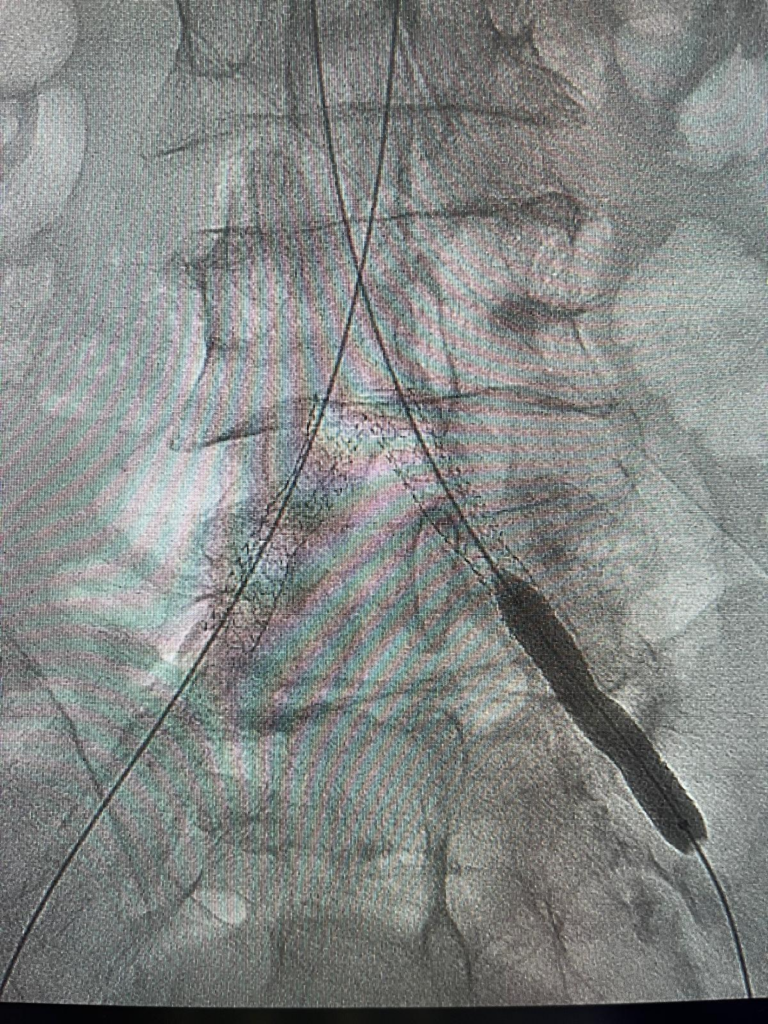

În cadrul procedurii au fost dilatate arterele afectate încă de la terminația aortei și rădăcina membrului inferior drept și au fost implantate 3 stenturi după pregătirea leziunilor țintă prin dilatare cu baloane de angioplastie. Două dintre stenturi au fost puse alăturate unul la celălalt la nivelul bifurcației aortei înspre membrele inferioare și s-a refăcut astfel această bifurcație care era afectată ateromatos sever și provoca simptomatologie invalidantă a pacientului. Al treilea stent a fost montat la nivelul arterei iliace care deservește membrul inferior stâng unde exista o îngustare semnificativă. Rezultatul final este unul bun cu circulația corectă a sângelui înspre membre.

Ajutorul oferit acestui pacient a fost posibil prin colaborarea excelentă în cadrul unei echipe mixte de cardiologie și radiologie, în cadrul programului național de Radiologie Intervențională coordonat de dr. Florin Grosu.